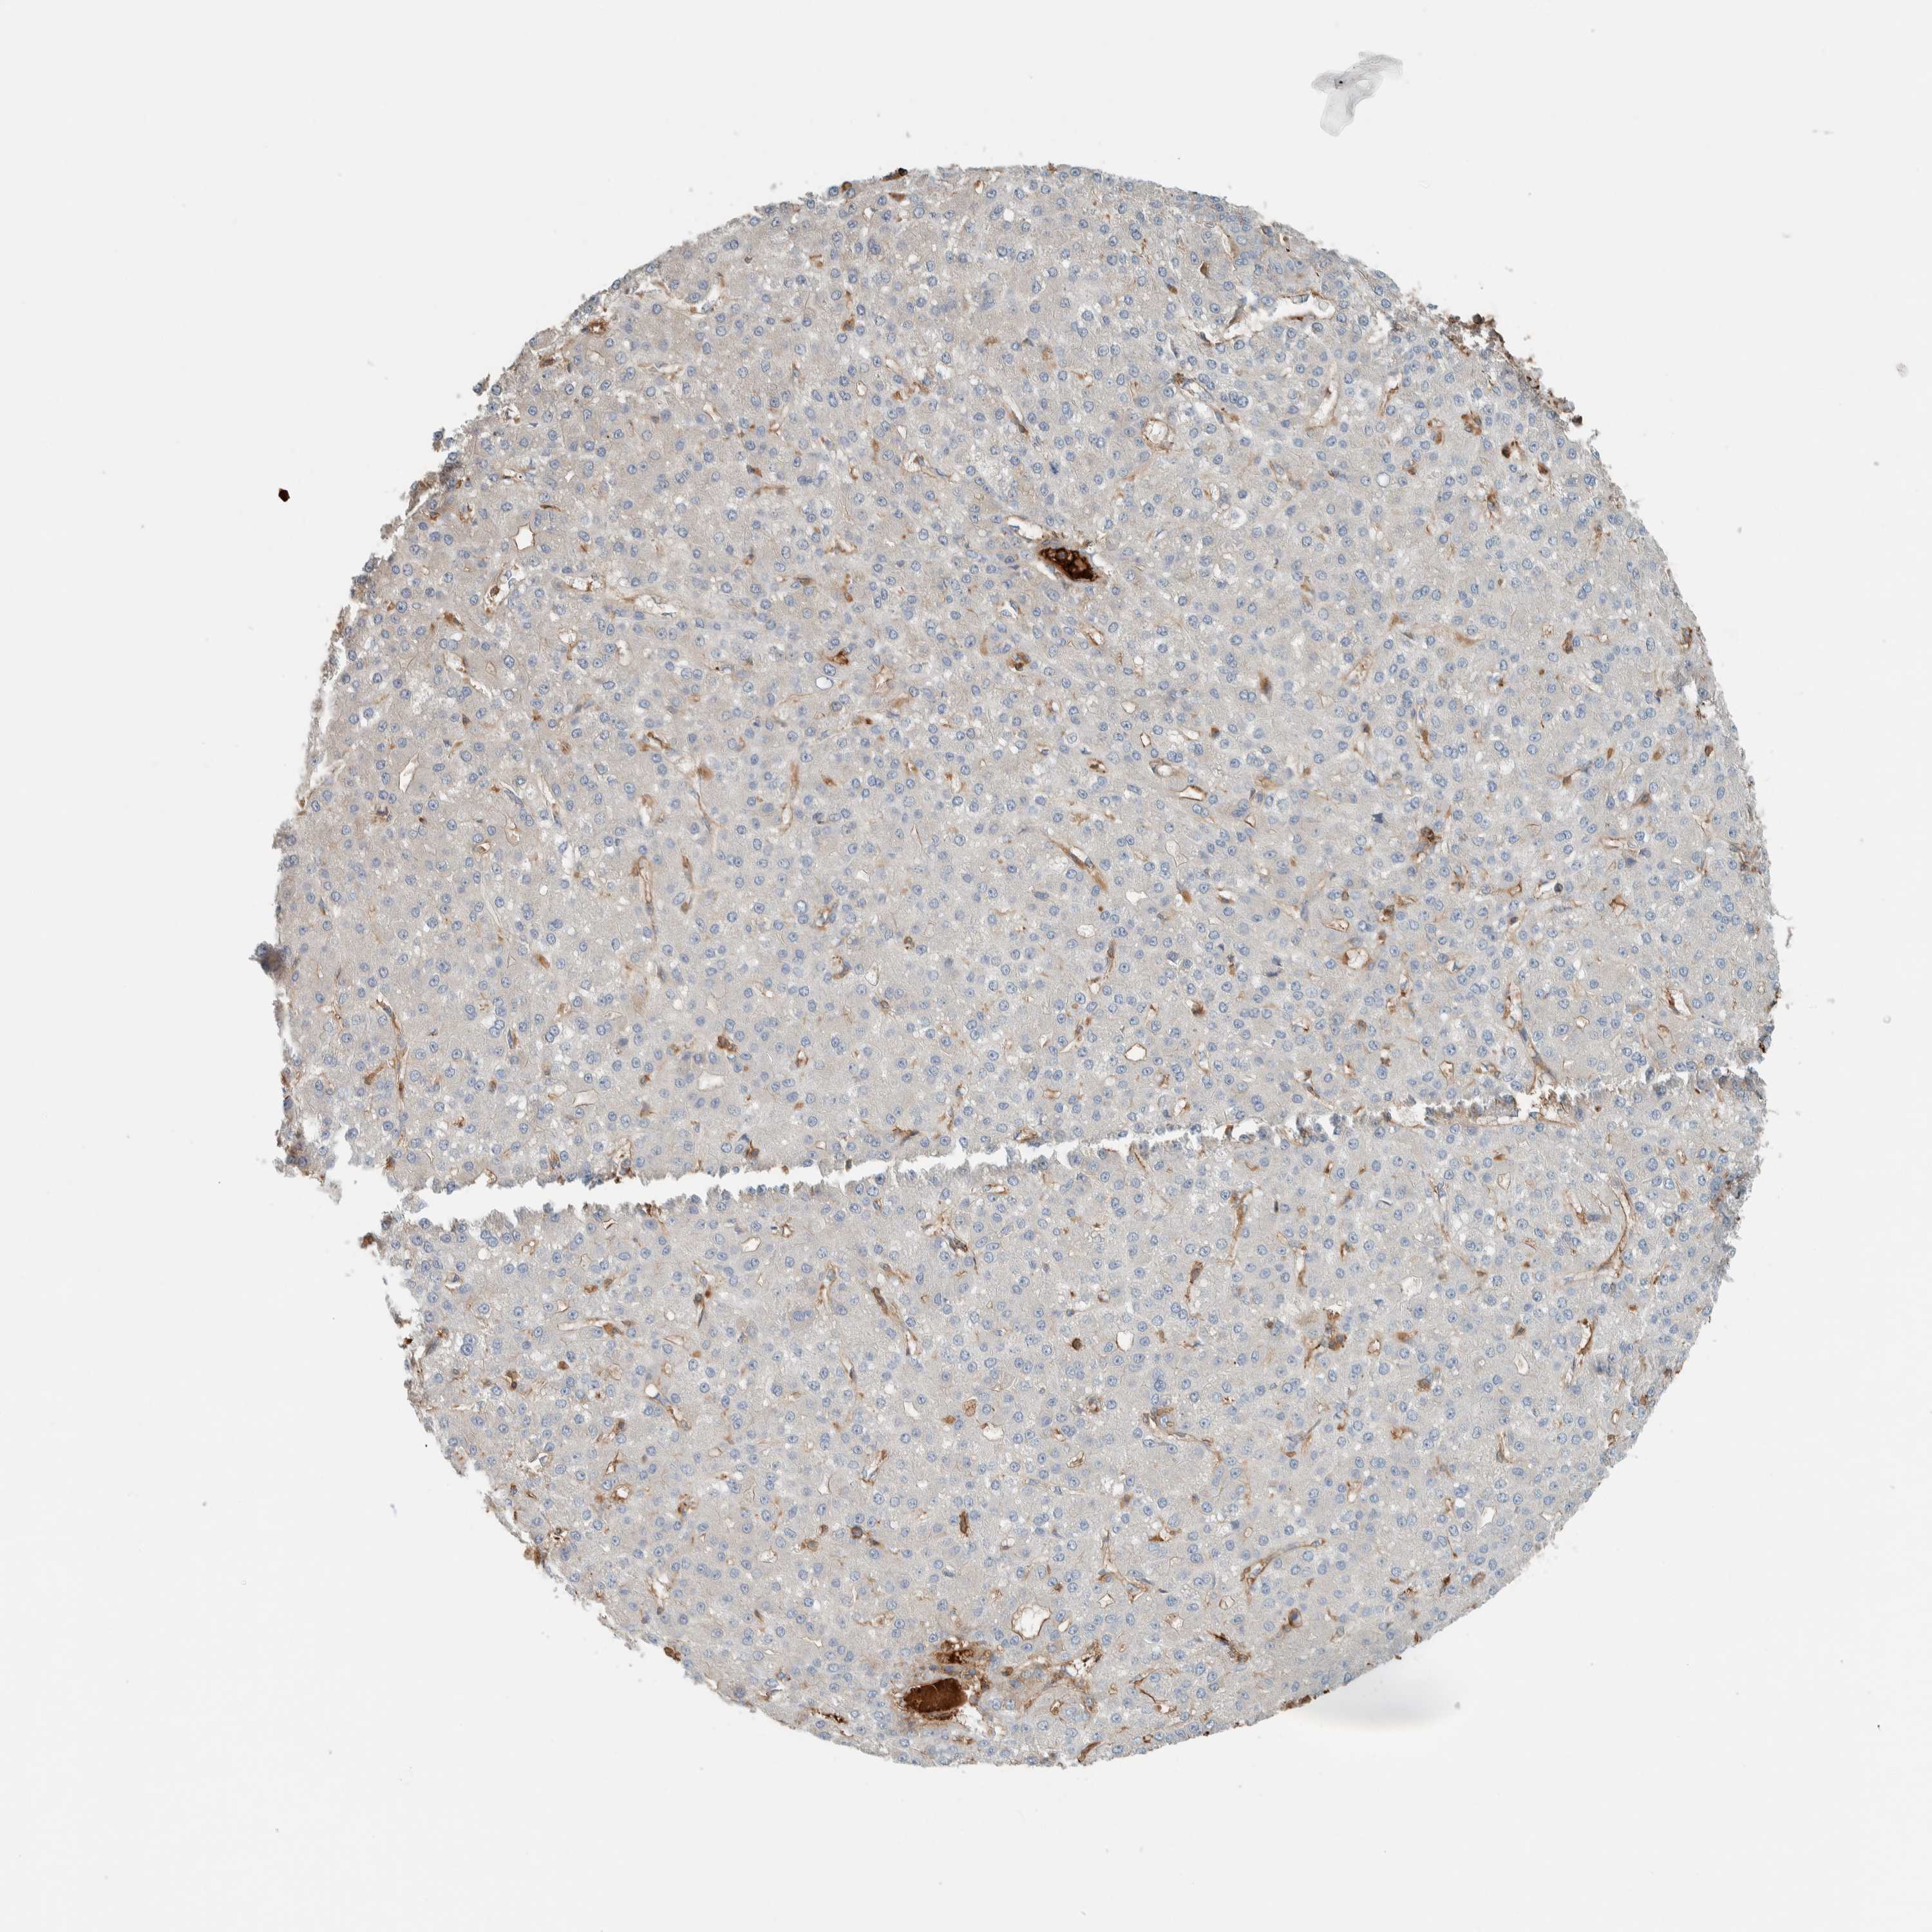

LIVER CANCER - Protein expressioni

A mouse-over function shows sample information and annotation data. Click on an image to view it in a full screen mode. Samples can be filtered based on level of antibody staining by selecting one or several of the following categories: high, medium, low and not detected. The assay and annotation is described here.

Note that samples used for immunohistochemistry by the Human Protein Atlas do not correspond to samples in the TCGA dataset.

Antibody stainingi

Antibody staining in the annotated cell types in the current human tissue is reported as not detected, low, medium, or high, based on conventional immunohistochemistry profiling in selected tissues. This score is based on the combination of the staining intensity and fraction of stained cells.

Each image is clickable and will lead to virtual microscopy that enables deeper exploration of all samples and also displays staining intensity scores, fraction scores and subcellular localization as well as patient and tissue information for each sample.

Antibody HPA023559

Antibody HPA023564

Antibody HPA044971

Antibody CAB031916

Cholangiocarcinoma

Carcinoma, Hepatocellular, NOS